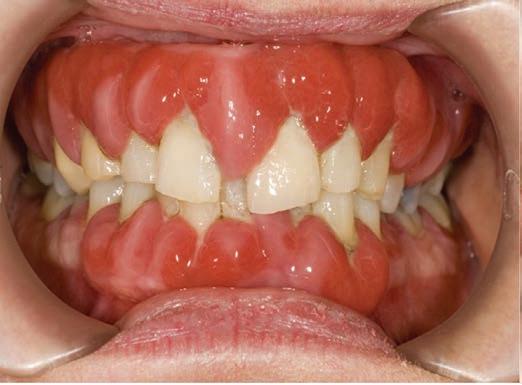

FIGURES 2 and 3: Drug-induced gingival hyperplasia.

Post-transplant management Following transplantation, recipients commit to lifelong immunosuppression therapy to prevent organ rejection (Figure 1). Immediately post transplant, induction therapy provides a high degree of immunosuppression. This is supplemented with antimicrobial agents to provide prophylaxis against bacterial and fungal infections. Subsequent lifelong immunosuppression is provided at lower doses during maintenance therapy (Table 1).5 Immunosuppressive medications can complicate oral health. Drug-induced gingival hyperplasia (Figures 2 and 3) caused by the immunosuppressive drug cyclosporin A is a common complication. This risk is further amplified if a patient is prescribed a calcium channel blocker (e.g., nifedipine), has poor oral hygiene and untreated periodontitis.6 Oral hygiene and the patient’s periodontal health play a decisive role in the level of manifestations of such gingival alterations. Oral hygiene education and non-surgical periodontal treatment play central roles in the management of drug-induced gingival overgrowth.7 Long-term immunosuppression increases patient susceptibility to pathological oral conditions (Table 2).8 Immunosuppressive drugs are thought to cause malignancy by a carcinogenic effect or by increasing the carcinogenic effect of other agents combined with an immunosuppressive effect.9 The importance of regular oral examinations is essential so that any dysplastic or malignant changes can be detected early.